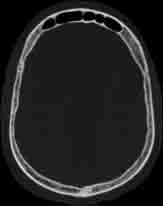

Visible Human male: Sectio transversalis 1058

CT